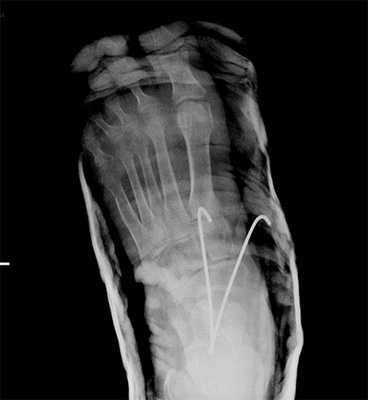

При смещении более 2 мм, нестабильности при функциональных тестах - рекомендовано открытое устранение вывиха с жёсткой фиксацией винтами или пластинами. Используются один или два продольных доступа в 1 и 2 межплюсневых промежутках. После обнажения первого предплюсне-плюсневого сустава первым этапом устраняется межклиновидная нестабильность, вторым этапом устраняется предплюсне-плюсневая нестабильность. В послеоперационном периоде сразу начинается разработка активного объёма движений. Нагрузку на стопу начинают постепенно, с тем чтобы полностью её восстановить к 6-8 неделе. Удаление спиц Киршнера производится через 6-8 недель, компрессирующих винтов через 3-6 месяцев. Возвращение к полной физической активности не ранее 9-12 месяцев после операции.

Открытое вправление вывиха, трансартикулярная фиксация 1-2-3 предплюсне-плюсневых суставов винтами.

В случаях этого повреждения показано оперативное лечение, открытое устранение подвывиха основания 2 плюсневой кости с фиксацией винтом. Устранение подвывиха производится из доступа в 1 межплюсневом промежутке, рубцовая ткань и остатки связки могут интерпонировать сустав, тогда потребуется их удалить. После вправления производится предварительная фиксация спицей и рентгенологический контроль.

Затем устанавливается винт соединяющий основание 2 плюсневой кости и медиальную клиновидную кость.

После осмотра в отделении ортопедии №2 ГКБ №13 принято решение о проведении операции - открытому устранению вывиха, артродезе 1-2-3 плюсне-клиновидных суставов, 1 межклиновидного сустава при помощи винтов и пластины, трансартикулярной фиксации спицами 4-5 плюсне-клиновидных суставов.

Первым этапом выполняется удаление костно-хрящевых экзостозов и рубцовых тканей из области всего сустава Лисфранка. После этого дистальный отдел стопы приобретает мобильность, достаточную для восстановления нормальной анатомии. Остатки суставного хряща полностью удаляются с 1-2-3 плюсне-клиновидных суставов, 1 межклиновидного сустава при помощи долота, осцилляторной пилы, кусачек Люэра, острой ложки Фолькмана. Для репозиции используются костные цапки.

Вершиной, ключом, блокирующим клином - в общем главной частью сустава Лисфранка является 2 плюсне-клиновидный сустав. По этой причине мы предпочитаем начинать фиксацию именно с него. Для артродеза используем винты с направленной в разные стороны резьбой FT Arthrex диаметром 4 мм. Они позволяют создать мощную межфрагментарную компрессию, а за счёт глубокой резьбы очень надёжно фиксируются в кости.

После восстановления 2 луча выполняем артродез межклиновидного сустава и 1 плюсне-клиновидного сустава. Учитывая что основная нагрузка ложится на 1 луч, дополнительно стабилизируем его при помощи пластины.